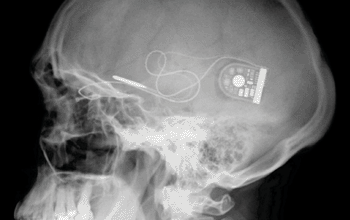

Wireless Signals Could Transform Brain Trauma Diagnostics